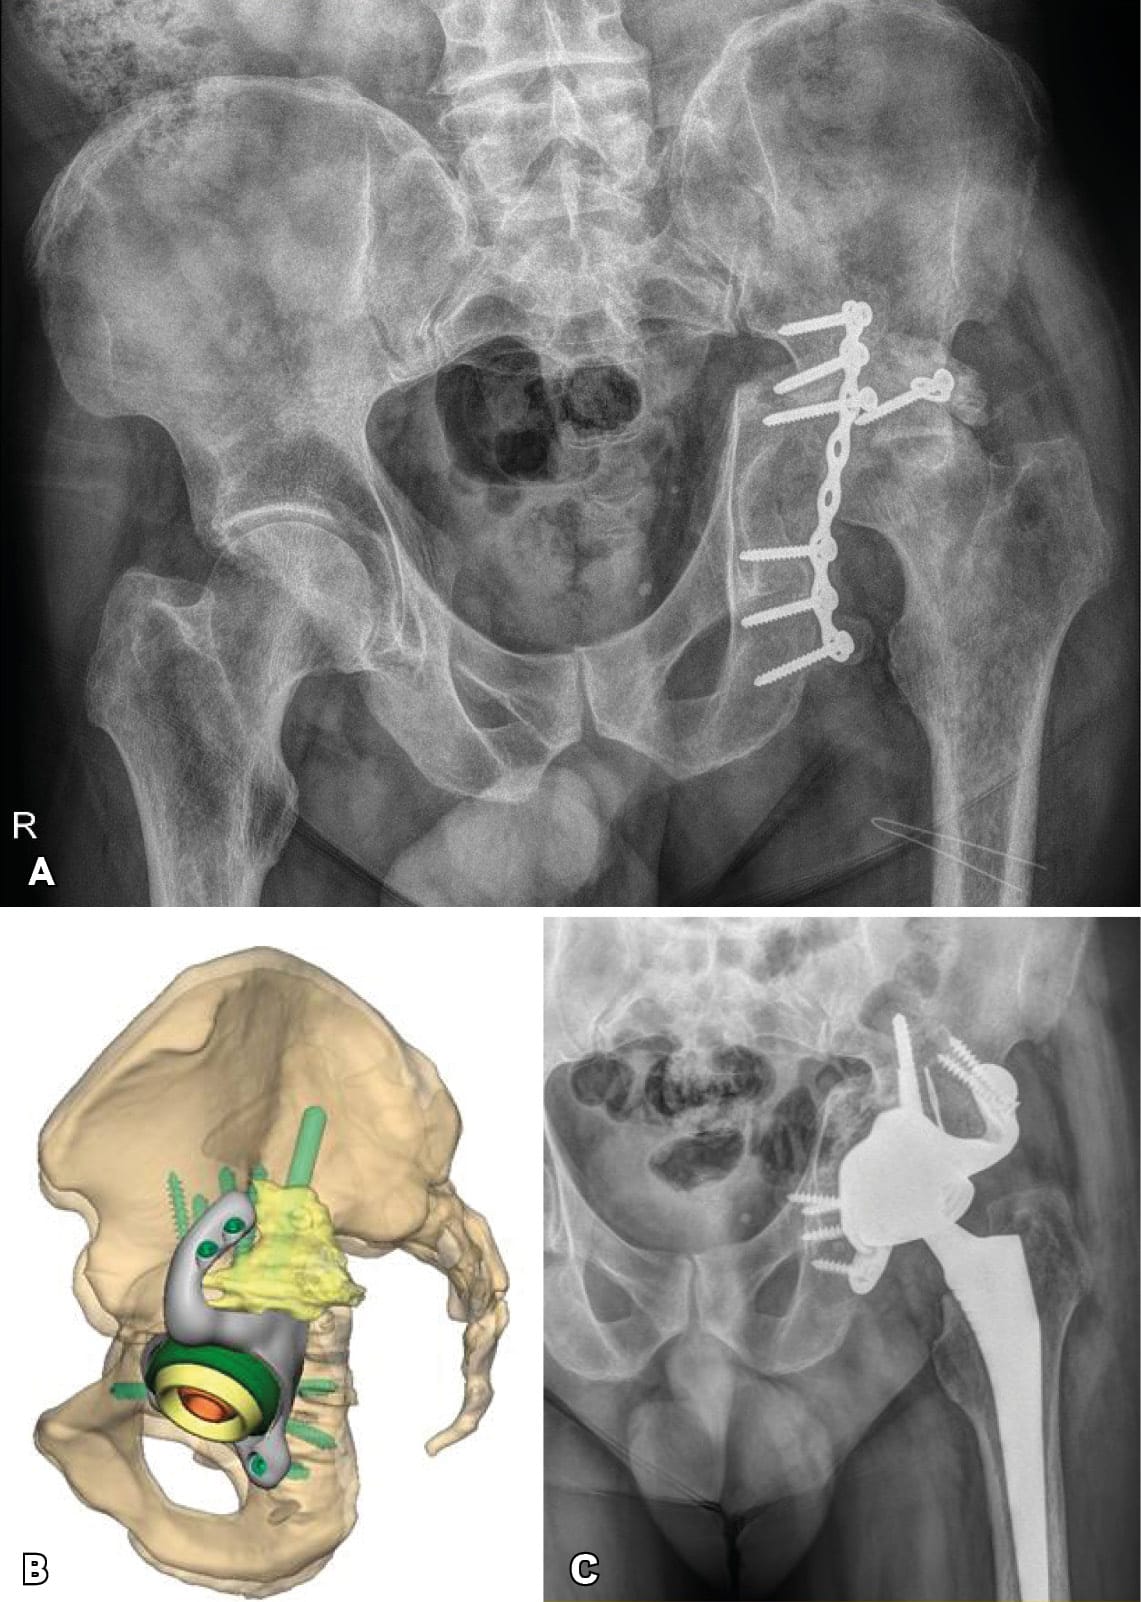

Severe post-operative defects. Principles of management and outcomes of specific patterns are not clearly reported in the literature. Based on the Sen clacification,[1] Sen RK, Mukhopadhyay R, Pattanshetti V, Saini G, Tripathy SK, Sethy SS, Sharma SK. A New Classification System for Acetabular Bone Defect Evaluation in Posttraumatic Acetabular Nonunion and Malunion. Indian J Orthop. 2022 Jun 27;56(9):1601-1612 types 1, 2, 3-A and 5 can be treated with surgical techniques used in revision THA surgery. For severe defects (such as 3-B, 4-A and 4-B), the restoration of hip center of rotation, cup offset, inclination and anterversion and hip stability can be achived only with custom-made implants (Figures 3 and 4).

Triflange and tumour like custom made acetabular impants. Modern technology allows the production of personalised implants for special conditions. These type of implants are custom made, porous coated titanium implants and are considered the last therapeutic salvage option, before excisional arthroplasty, for severe acetabular defects and PD. The implants are designed and manufactured based on pelvic models created by thin-slice pelvic 3-D CT-scans with metal subtraction software (Figures 7 and 8). Early and mid-term outcomes are encouraging but premium cost and length of production time limit their use.[20], DeBoer DK, Christie MJ, Brinson MF, Morrison JC. Revision total hip arthroplasty for pelvic discontinuity. J Bone Joint Surg Am. 2007; 89(4):870-876.[21], Taunton MJ, Ferhing TK, Edwards P, Bersasek T, Holt GE, Christie MJ. Pelvic discontinuity treated with custom triflange component: a reliable option. Clin Orthop Relat res. 2012; 470(2):428-434.[22] Zhang Y, Gao Z, Zhang B, Du Y, Ma H, Tang Y, Liu Y, Zhou Y. The application of custom-made 3D-printed titanium augments designed through surgical simulation for severe bone defects in complex revision total hip arthroplasty. J Orthop Traumatol. 2022; 6:23(1):37.